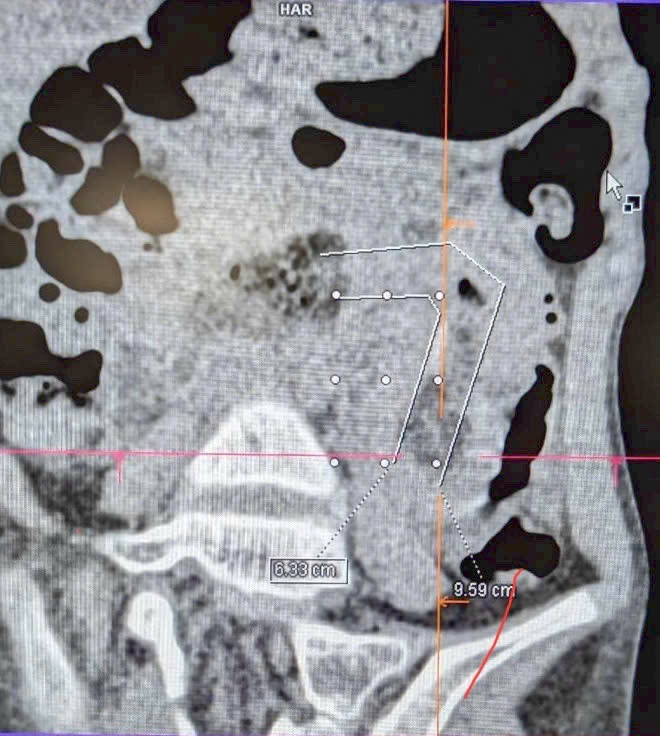

CT scan images confirmed the presence of the hairball and intestinal obstruction in the patient.